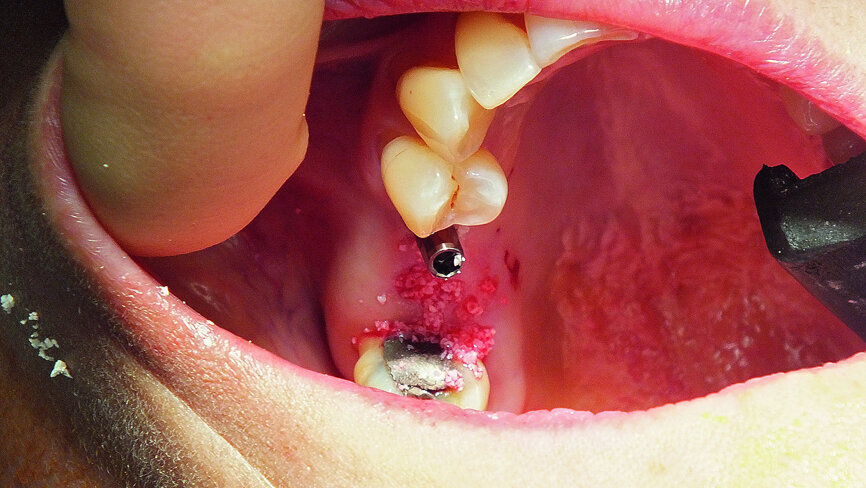

Fig. 6: Preparation of upper right second premolar implant site.

Treatment was carried out under local anaesthesia. The flapless procedure resulted in minimal trauma to the gingival tissue overlying the ridge. The previously constructed NaviStent, and the drill tag and jaw tag supplied by ClaroNav, were prepared immediately prior to surgery (Fig. 3). In accordance with the Navident protocol, the axis of the drill and tip of the pilot drill were calibrated (Figs. 4 and 5) and verified before site preparation commenced (Fig. 6). Using computer-guided surgery, the pathway of the drill could be followed clearly on the computer screen positioned in front of the patient (Fig. 7). Approximately 1 mm of bone was left intact in the upper right first molar site ready for the sinus lift. Navident provided visual confirmation of the position of the drill tip to accurately gauge the correct depth (Fig. 8). Preparation continued using a 3.5 mm drill bit, which, again, was calibrated and verified before use (Figs. 9 and 10).

A 3.5 mm diameter and 8 mm length Dentsply Ankylos C/X implant was placed 1 mm subcrestally in the upper right second premolar site. A guide pin was placed in the upper right first molar site to check the depth and alignment (Fig. 11). The NaviStent was removed and the site was prepared for the sinus lift osteotome (Figs. 12 and 13). The osteotome was tapped gently with a surgical mallet until the remaining thin layer of bone infractured and was elevated (Fig. 14). The Schneiderian membrane was carefully raised through manipulation with the osteotome and a heterogeneous bovine bone graft material (Bio-Oss, Geistlich) was introduced into the implant site (Fig. 15). A 4.5 mm diameter and 6.6 mm length Ankylos C/X implant was then placed 1 mm subcrestally (Figs. 16 and 17). Both implants had good primary stability on placement. Ankylos Balance posterior sulcus formers were fitted, without the need for additional closure with sutures (Fig. 18).